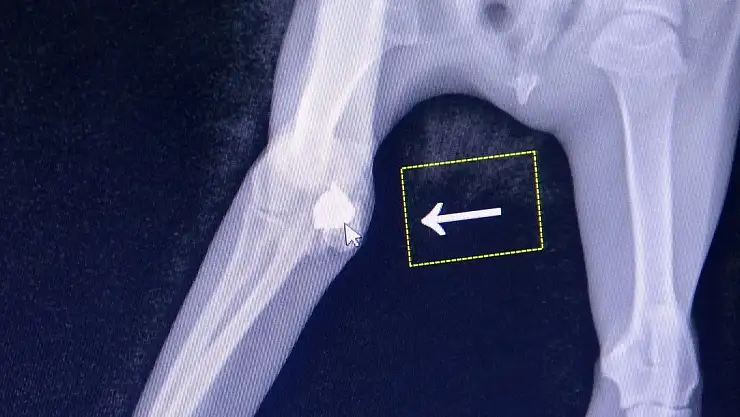

Keşan'a bağlı Erikli köyü sahilinde sağ ön bacağını kullanamayan ve topallayarak yürüyen yavru kediyi gören hayvanseverler, durumu Keşan Sokak Hayvanlarını Koruma Derneği (KE-HAYKO) yetkililerine bildirdi. Dernek yetkililerince Erikli köyü sahilinden alınan yavru kedi, Keşan'daki özel bir kliniğe getirildi. Burada yapılan muayene ve çekilen röntgen filminde yavru kedinin havalı tüfekle sağ ön bacağından vurulduğu ve saçmanın diz kapağına girmesi sonucu yaralandığı belirlendi. Saçma çıkarılamazken, yavru kedinin ömrü boyunca topallayarak yürümek zorunda kalacağı bildirildi.

Veteriner Hekim Berk Canbaz, yavru kedinin kendilerine trafik kazası geçirdiği gerekçesiyle getirildiğini ancak yapılan tetkiklerde sağ ön bacağından havalı tüfekle vurulduğunun belirlendiğini ifade ederek, "Ayağında topallama şikayetiyle geldi. Yapılan muayeneden sonra röntgen çektik. Röntgen sonucunda da sağ ön bacağı diz kapağı bölümünde saçma olduğunu gördük. Ekleme saplanmış bir şekildeydi. Müdahale edilebilecek veya operasyonla çıkarılabilecek bir durumda değildi. Topallama şikayeti devam edecektir ama o bölgeye müdahale etmemiz mümkün değil. Yaptığımız incelemede gördük ki havalı tüfekle vurulmuş. Ömür boyu bu saçmayla yaşamak zorunda kalacak. Çünkü saçmayı o bölgeden aldığımızda eklemin dağılması söz konusu. Bu da bacağını kaybetmesine kadar gidebilir. Maalesef ömür boyu topallayarak yaşayacak" dedi.